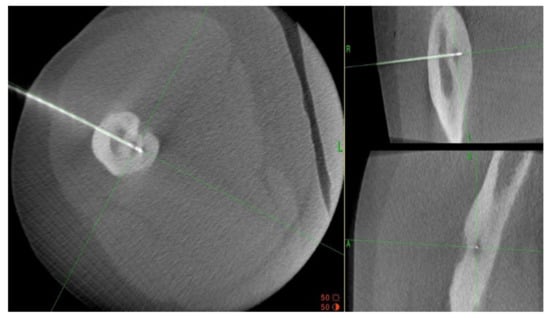

- Wałejko, S.; Mazurek, T.; Żychliński, M. Bifocal osteoid osteoma of the talus treated with thermal ablation and navigation 3D—Case report. Chir. Narz. Ruchu Ortop. Pol. 2020, 85, 25–28. [Google Scholar] [CrossRef]